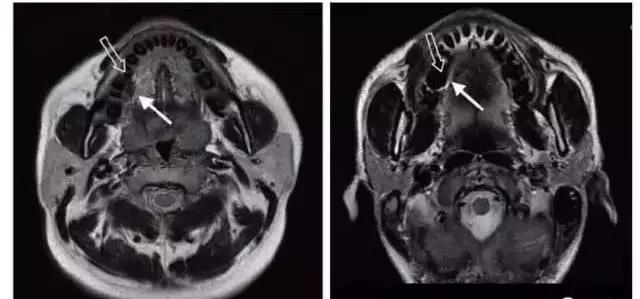

如果是口腔的金屬修複體(ti) ,會(hui) 影響到腦部、頸部、麵部等部位的成像結果,也就是在片子上會(hui) 有一個(ge) 黑色的偽(wei) 影,而這個(ge) 偽(wei) 影可能會(hui) 影響醫生進行正確的判斷,純鈦烤瓷牙無磁性,可以透X光,所以是沒有的多大影響的,所以不用擔心,但是材料必須是正規的純鈦,而不是鈦合金材料。